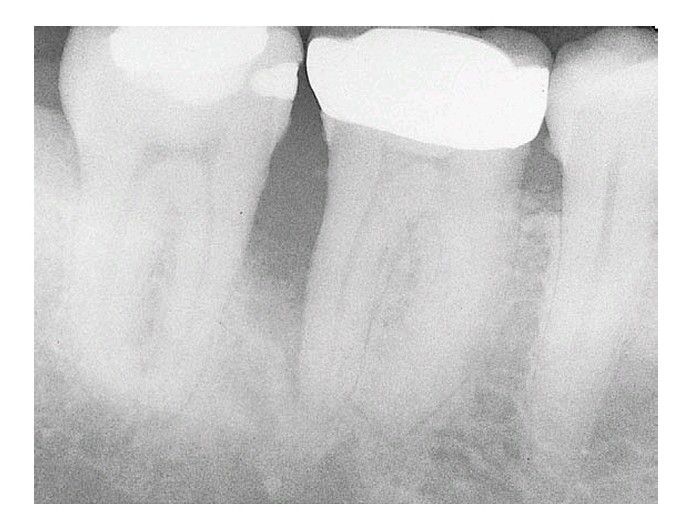

Tooth #30 has a poor prognosis. Periodontal probing reached the apex of the distal root. Extraction is indicated and should be done as soon as possible to prevent further damage to the mesial bone associated with tooth #31. Implant site preservation is another con sideration in treatment planning for this case.